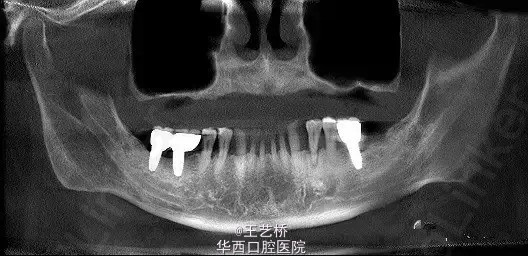

各式各样形态的上颌窦(一)

在进行上颌后牙区种植手术时,上颌窦形态是我们需要考虑吧的重要因素之一。今天收集了众多上颌窦的影像片,供大家交流学习。